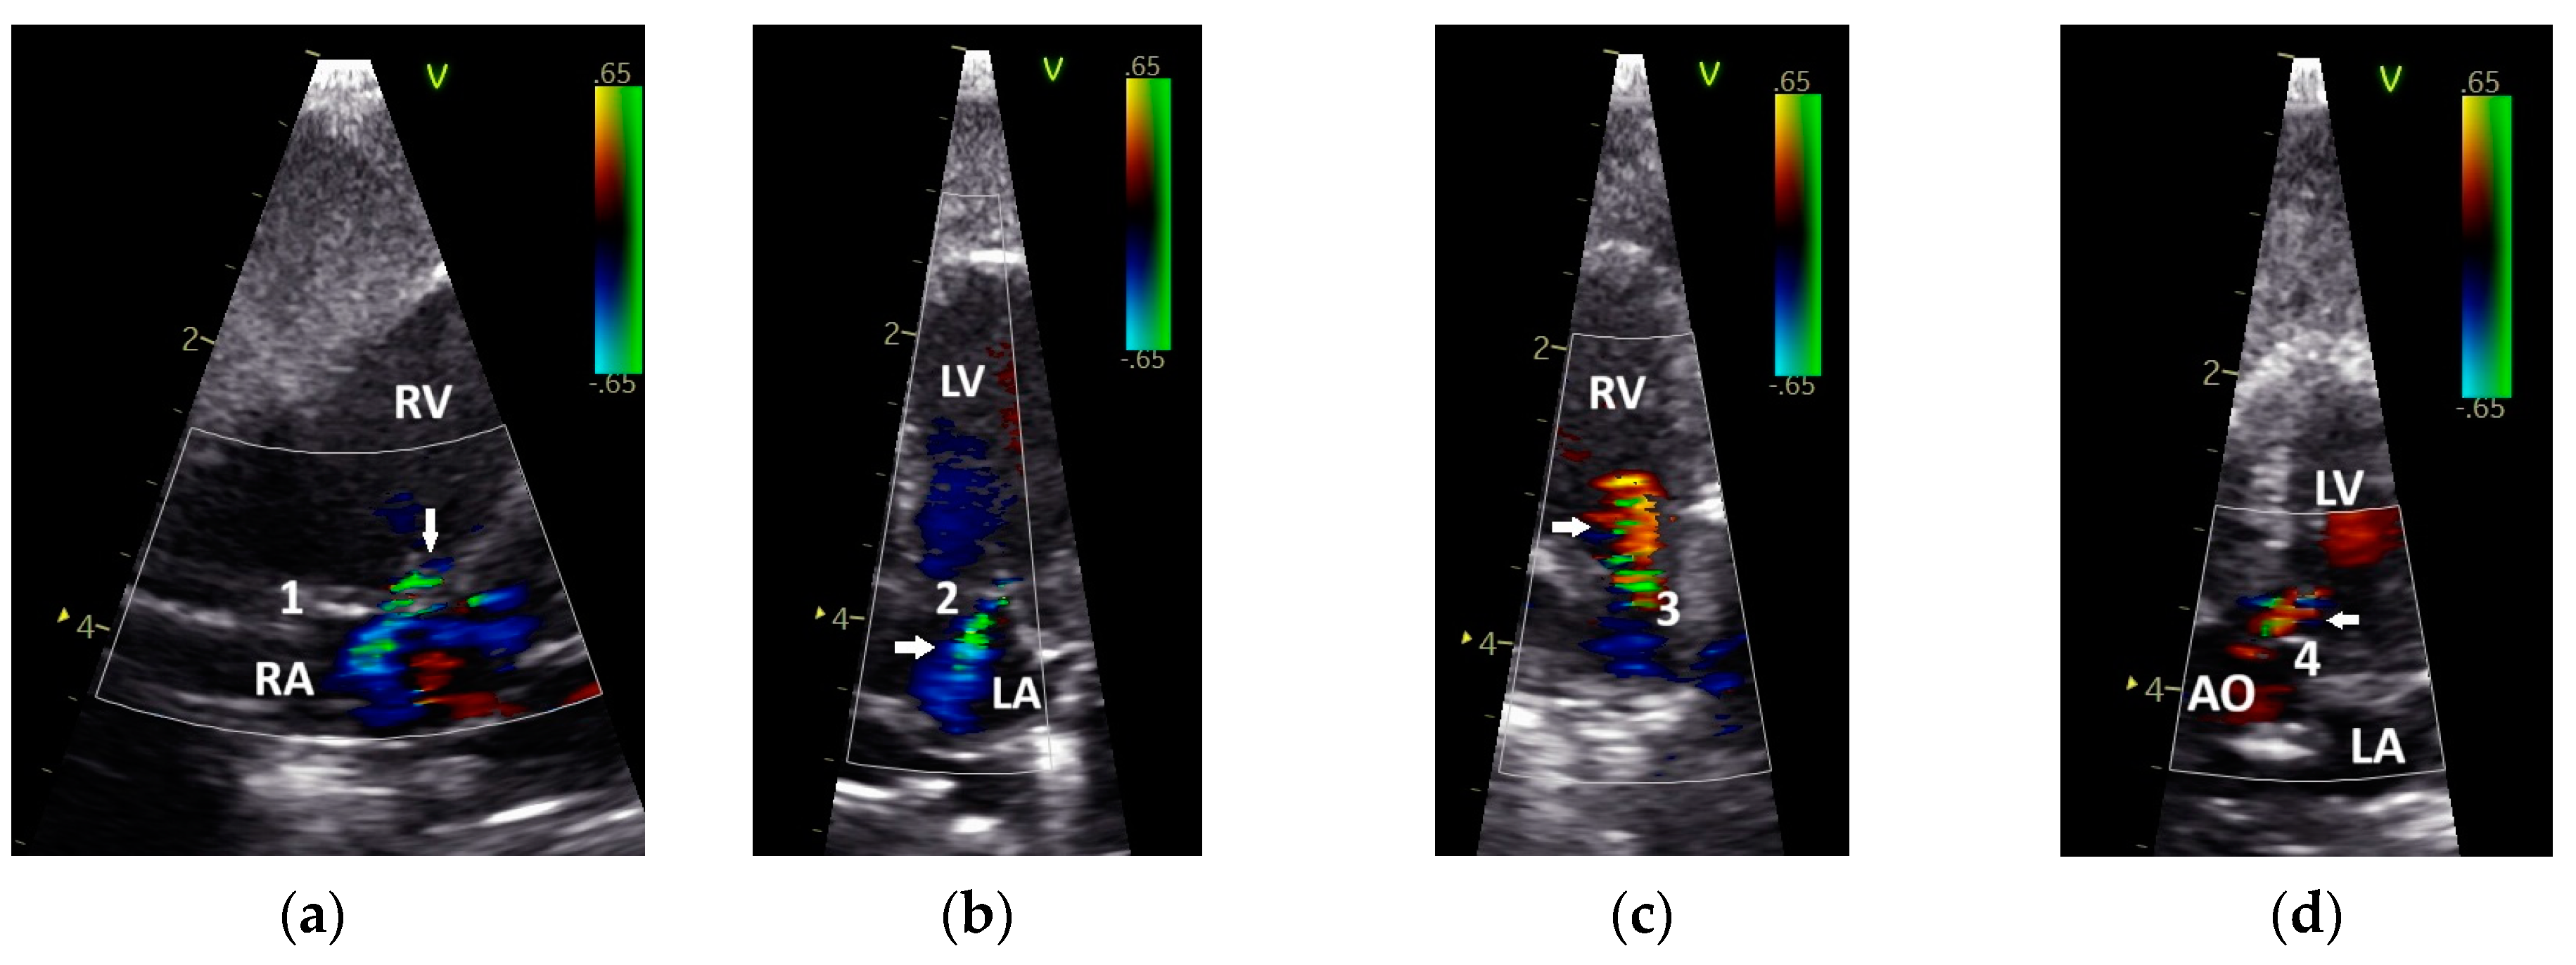

3.1. Shape of PAFP and AOFP of Grey Parrots

3.2. The Influence of Heart Failure on the Shape of the PAFP and AOFP

3.3. Influence of the Heart Rate on the Pulmonary and Aortic Blood Flow Profiles of the GPs

3.4. Correlation of Diastolic and Systolic Blood Flow Velocities with the Shape of the Pulmonary and Aortic Blood Flow Profiles in the Examined Diseased Grey Parrots